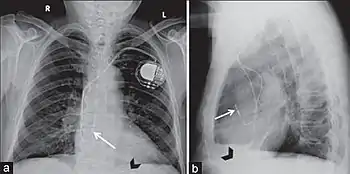

Posteroanterior and lateral chest radiographs of a pacemaker with normally located leads in the right atrium (white arrow) and right ventricle (black arrowhead), respectively.

Placement of internal pacemakers and defibrillators are done through catheterization as well. An exception to this is placement of electrodes on the outer surface of the heart (called epicardial electrodes). Otherwise, electrodes are placed through the venous system into the heart and left there permanently. Typically, these devices are placed in the left upper chest and enter the left subclavian vein and electrodes are placed in the right atrium, right ventricle, and coronary sinus (for the left ventricle stimulation).